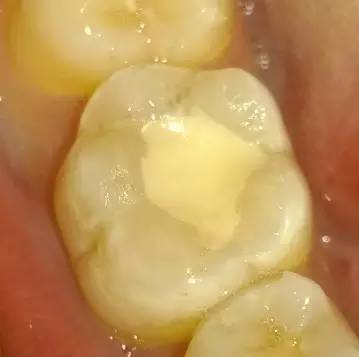

银汞填充物能掩盖龋齿

由于X光无法穿透银汞填充物,所以医生就很难发现小的新发生的龋坏部位。

研究表明,在给补过牙的病人做检查时,医生如果不使用X光,就只能看到50%的龋齿,即便使用全套X光也只能看到80%至85%。因此,有接近20%的龋齿被金属阻挡而看不到。

所以,不去除原来充填的金属,医生难以决定是需要重新补牙,还是需要更进一步进行根管治疗。

银汞填充物可能导致牙齿出现裂缝

牙齿裂缝也是牙医需要考虑的问题,因为X光片也会显示不佳。

牙齿裂缝在四五十岁的病人身上很常见。曾有病人在十几岁时补过牙,结果在前不久的检查中医生发现补过的牙上面出现裂缝。这个病人牙齿敏感,这说明裂缝可能深及神经,所以必须安装牙冠把牙齿保护起来。他的牙齿上没有新的龋坏,只有随年龄的增长不可避免的磨损。